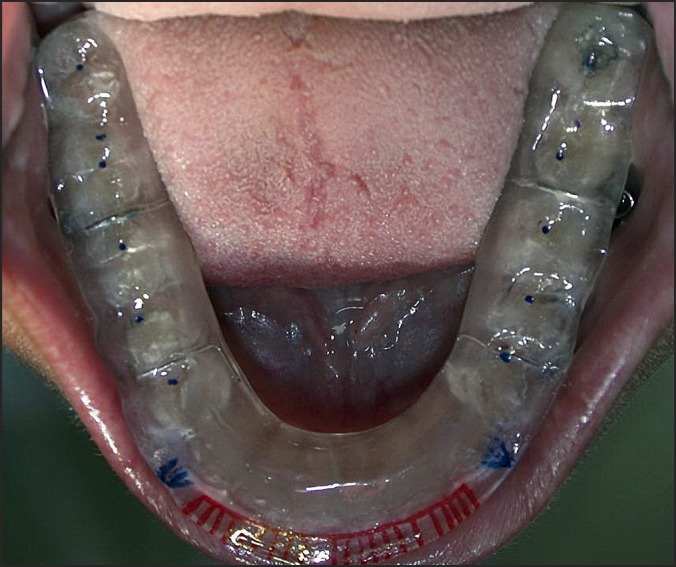

Methods: No surgical treatment was performed. A functional therapy was applied with a jaw splint. A closed treatment for mandibular condyle fractures was preferred because the amount of condylar displacement wasn't considerable.

Conclusions: The current case report and literature review showed that non-surgical therapy of neck-condylar fracture in a child with lower resin splint can restore mandibular movements and aesthetics. Facial growth after one year treatment resulted normal. A conservative treatment may be appropriate for children in selected cases with minimally displaced condyle.